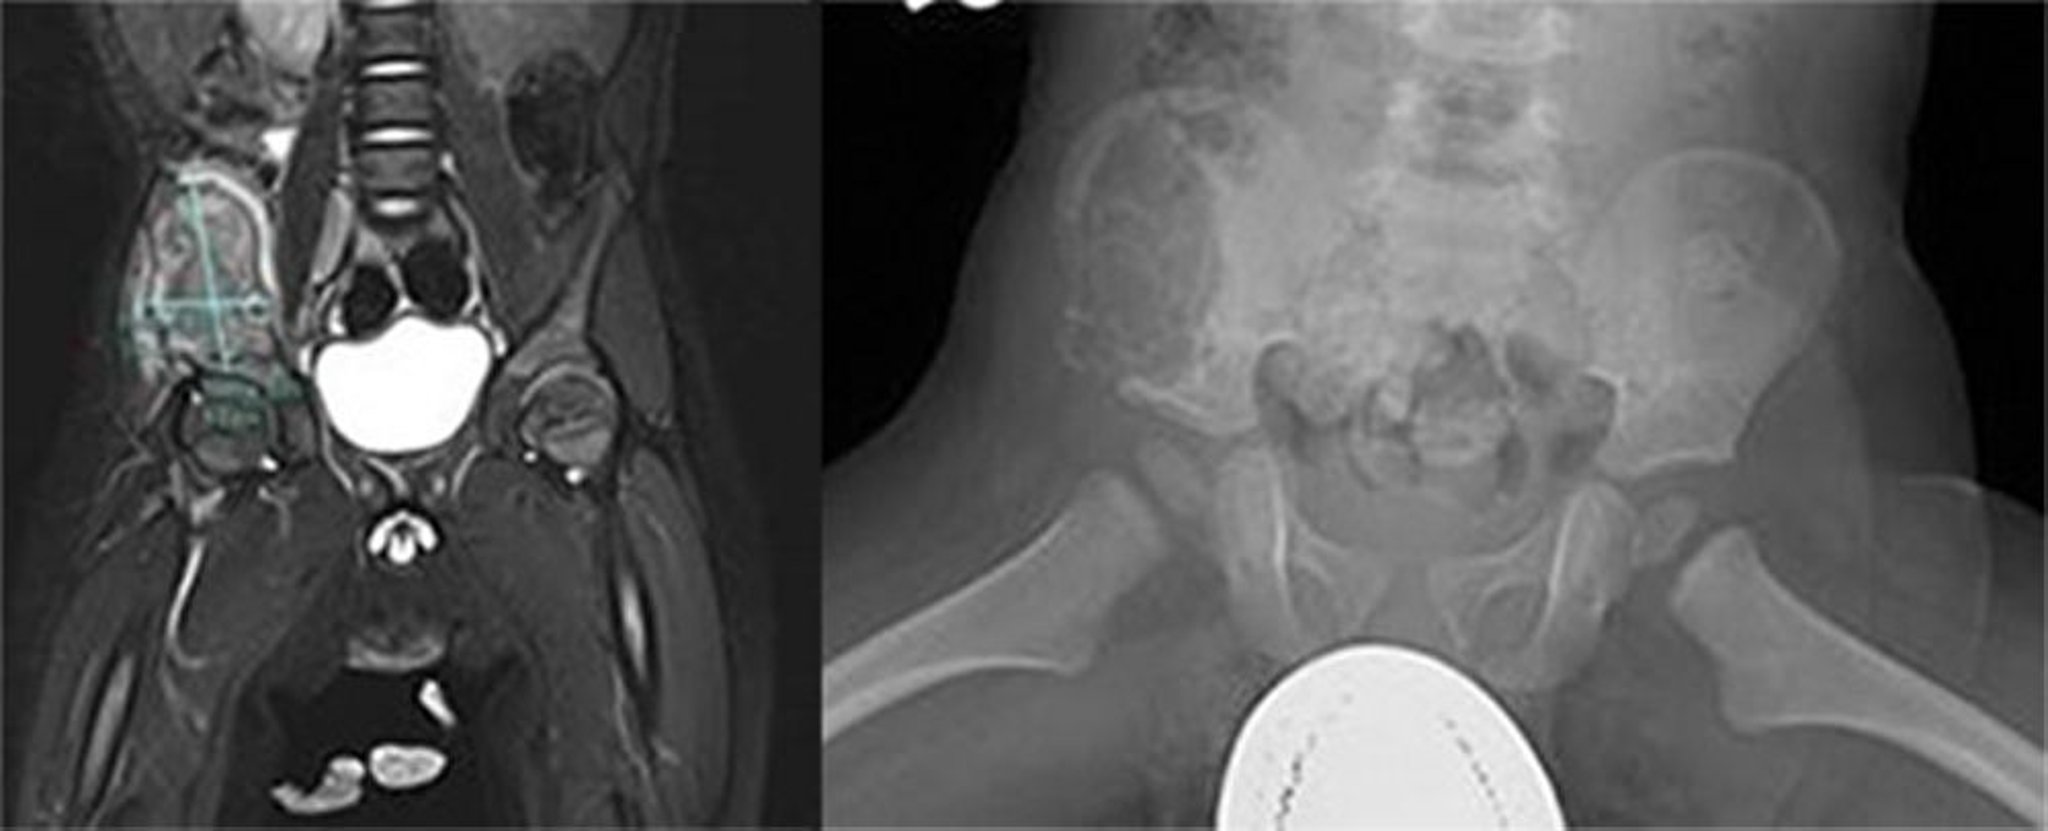

Histiocitosis de células de Langerhans (hueso pelviano)

Esta imagen muestra una gran lesión agresiva dentro del ala ilíaca derecha. Una RM reveló que la masa era heterogénea en T2 con baja señal T1y realce heterogéneo de la masa y la musculatura circundante con desviación medial del psoas derecho, lo que sugiere una lesión ósea agresiva (izquierda). En la radiografía (derecha), se observó una gran lesión lítica dentro del ala anterior y lateral del íleon que se extendía por delante y por debajo del isquion. Se observa la corteza expandida e irregularidades corticales. La biopsia fue diagnóstica para histiocitosis de células de Langerhans.